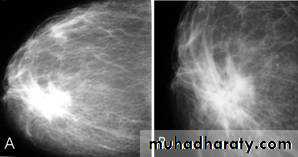

A…..Invasive ductal carcinoma is a subset of ductal carcinoma. It is an infiltrating, malignant and abnormal proliferation of neoplastic cells in the breast tissues. It is the most frequently seen breast malignancy .

Radiographic features

Mammogram

spiculated hyperdense lesion

oval/lobulated lesion

microcalicifications

Infiltrating or invasive lobular carcinoma (ILC) of the breast is the second most common type of invasive breast cancer after invasive ductal carcinoma (IDC) .

ILC is more often multicentric and bilateral (10-15%). Therefore imaging evaluation of the contralateral breast is crucial. There can be very subtle changes such as progressive shrinkage or enlargement or reduced compressibility of the involved breast. Imaging often underestimates the disease.

Mammography

The sensitivity of mammography for the detection of ILC reportedly ranges between 55-80% 8. Because of the limitations of mammography in detecting ILC, other modalities, such as sonography and MR imaging, are being used in evaluating clinically suspicious findings and known cancers to assess the extent of disease. ILC are more commonly seen on the craniocaudal (CC), compared to the mediolateral oblique (MLO).

Invasive ductal Ca invasive lobular CA